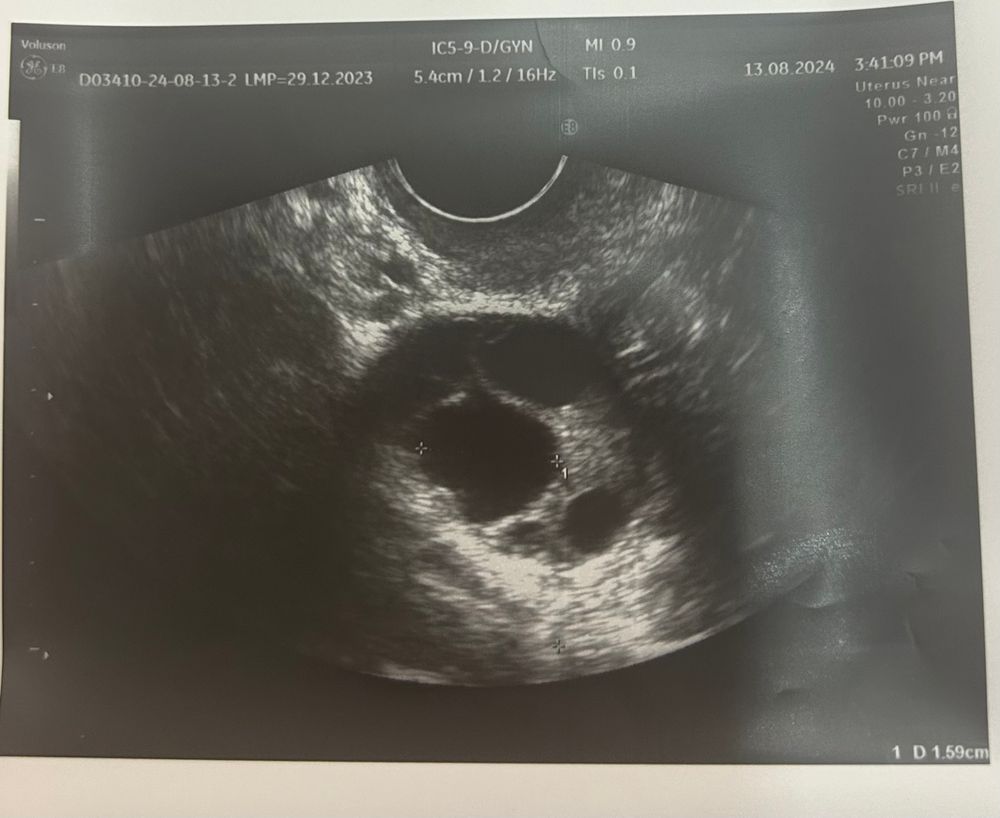

Всем добрый вечер! Сегодня 11-й дц, была на фолликулометрии, яичники дали ответ на стимуляцию клостилбегитом, ДФ 17 мм в правом яичнике. Но эндометрий тонкий, 5мм, с 14 дц назначили эстрожель и после овуляции свечи уторжестан 200 мг. Для улучшения передвижения спермиков купила актиферт гель. Надеюсь, что МФ не подведет.